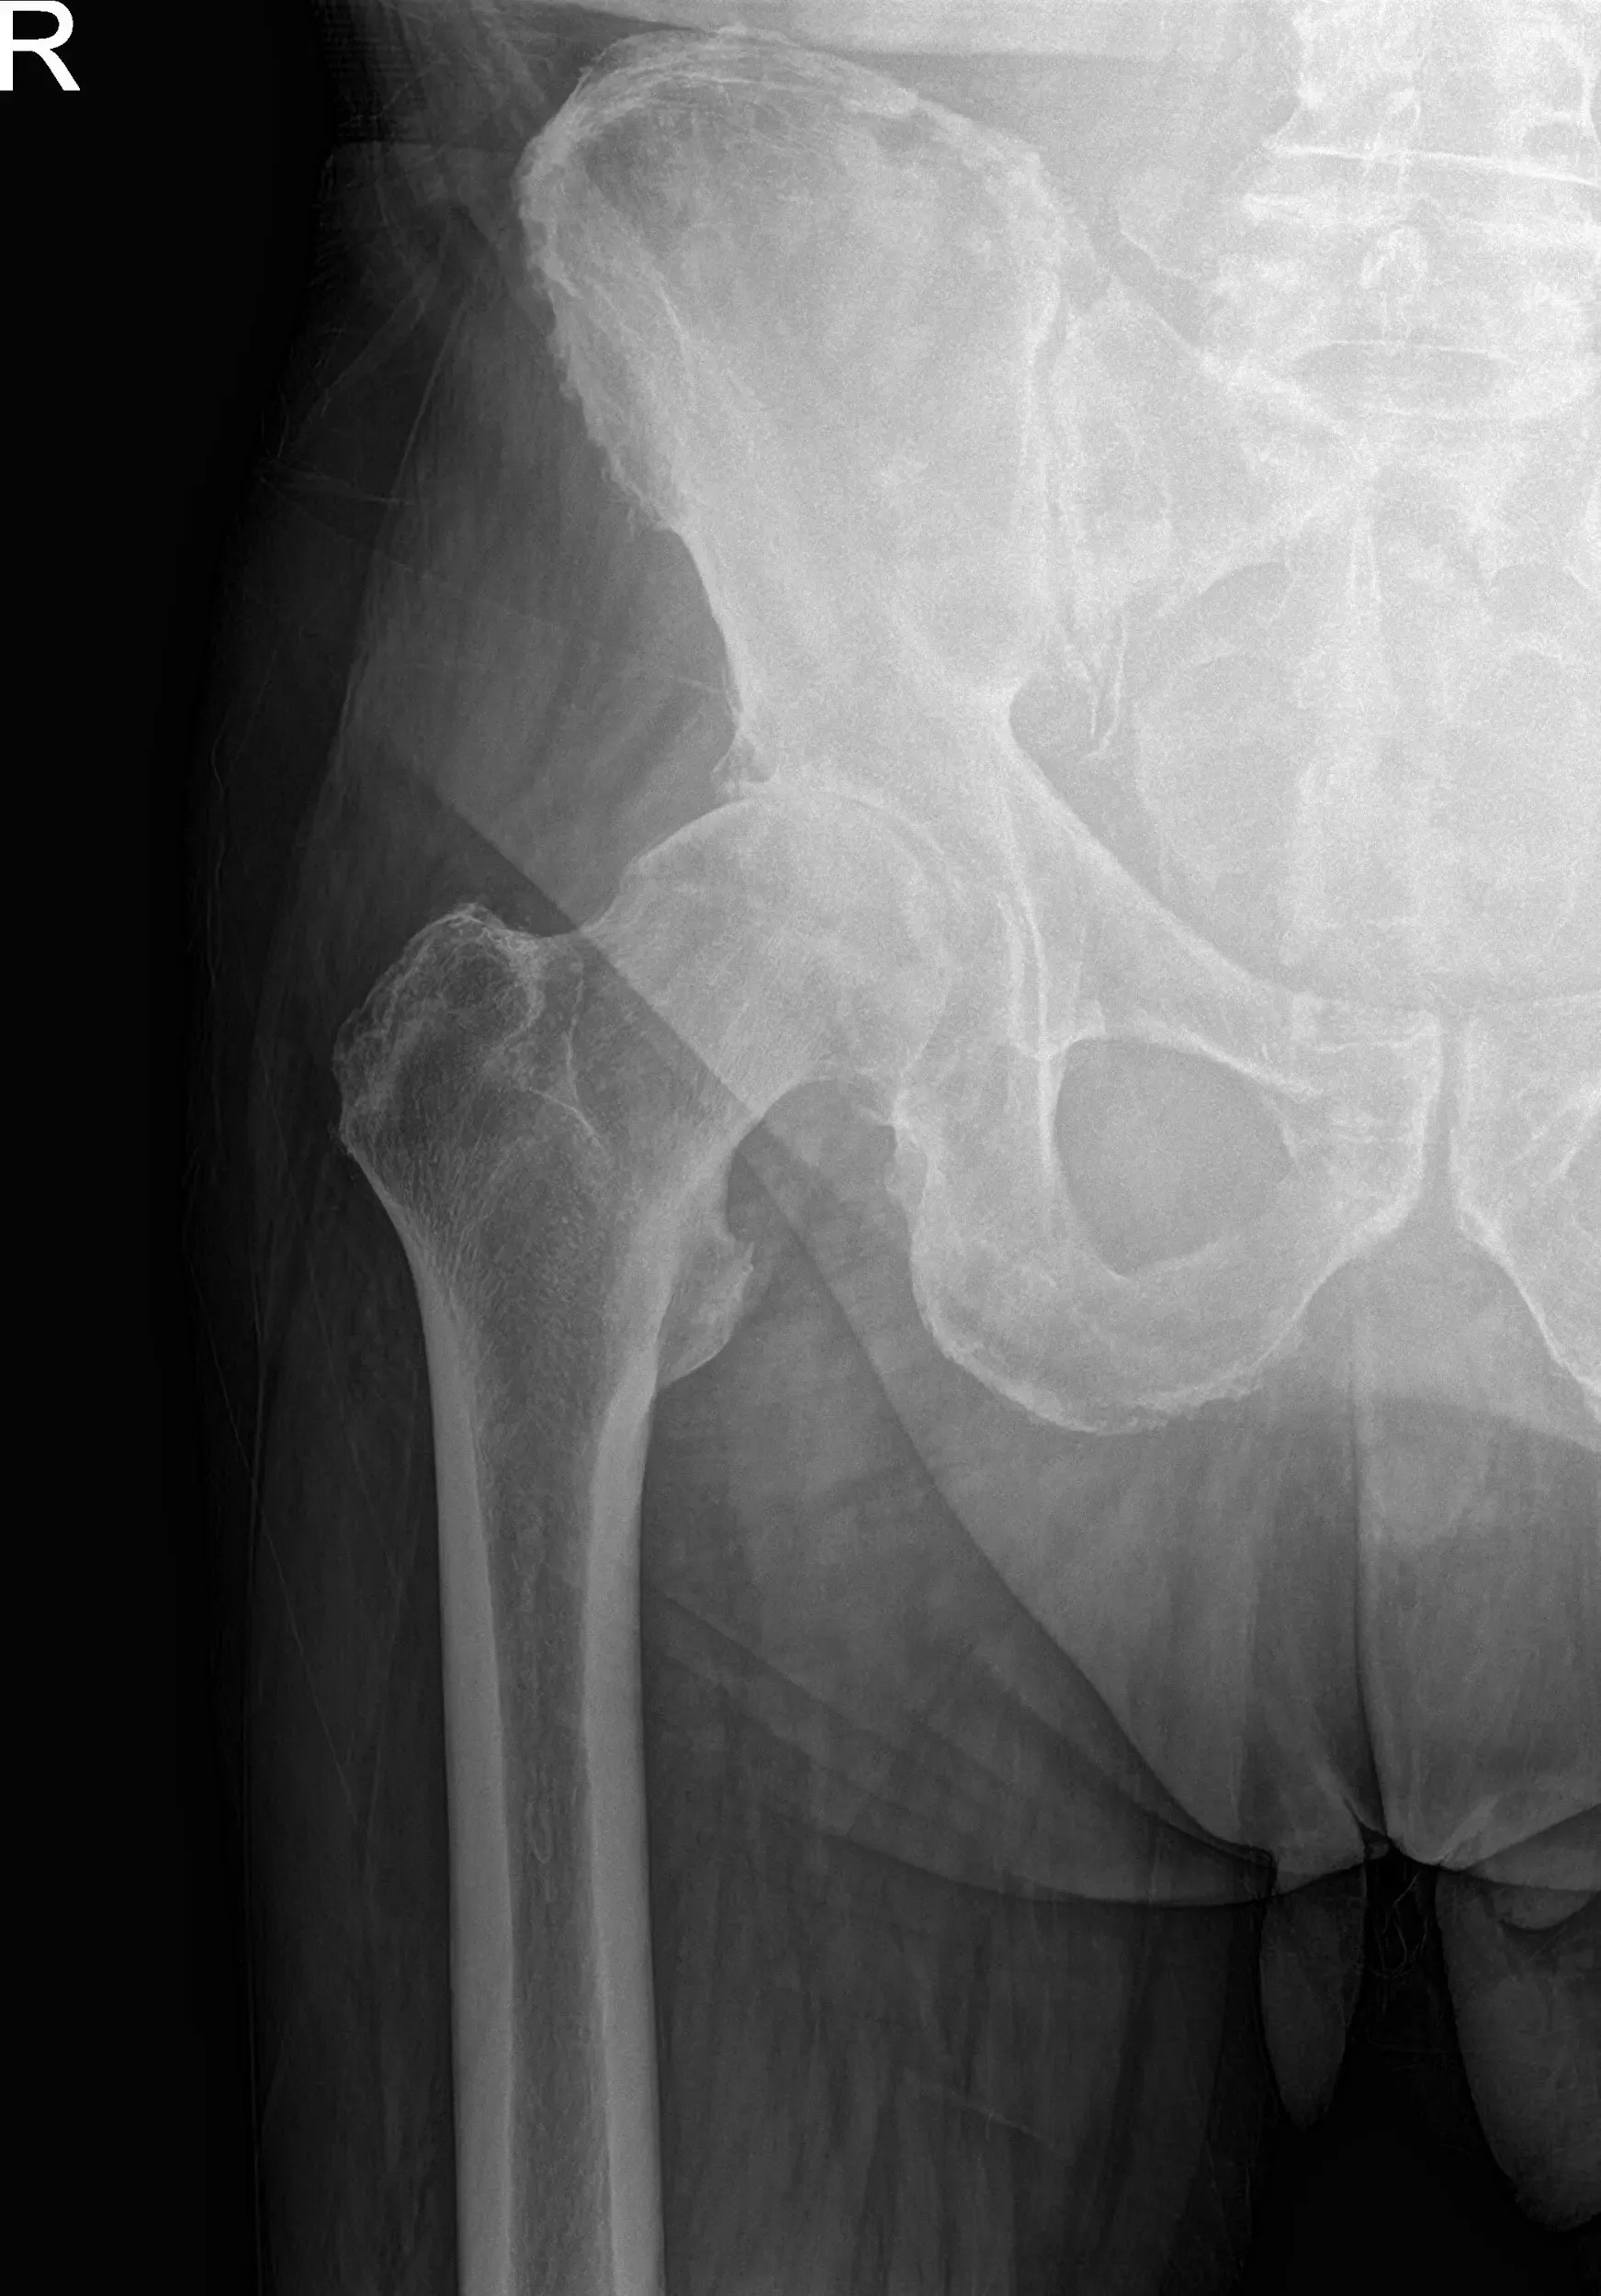

Radiographs of the pelvis revealed osteoarthritic changes in the right hip. Considering her comorbidities and lifestyle limiting hip pain, she was advised a total hip replacement surgery. She was made aware of the added risk of the surgery owing to atrial fibrillation and hypertension.